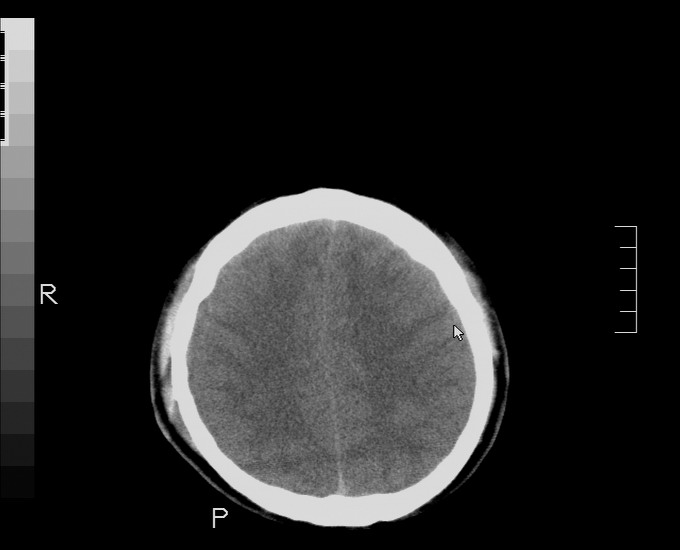

以下是引用随光逐影在2010-4-11 11:00:00的发言:[br]1)左侧额颞顶部硬膜下血肿。2)蛛网膜下腔出血。3)右侧颞顶部颅骨线形骨折。[br][br]20小时后复查:左侧额颞叶脑挫裂伤;左侧额颞顶部硬膜下血肿及蛛网膜下腔出血有吸收表现;右侧颞顶部颅骨线形骨折。[br]